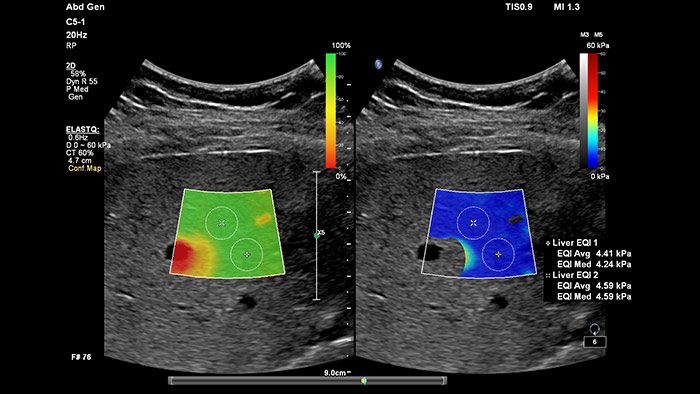

La elastografía por ultrasonidos de onda transversal ofrece un método no invasivo, reproducible y fácil de poner en práctica para evaluar la rigidez tisular. Los estudios realizados apuntan a que, en lugar de un costoso y doloroso procedimiento de biopsia, una sencilla exploración por ultrasonidos con elastografía de onda transversal podría convertirse en el procedimiento habitual para evaluar el estado de las enfermedades hepáticas. La elastografía por onda transversal de alto rendimiento de las imágenes con ElastQ incluye la evaluación cuantitativa de la rigidez tisular, codificada con colores, en extensas regiones de interés (ROI) en tiempo real. Las imágenes con ElastQ también ofrecen la posibilidad de efectuar mediciones retrospectivas en imágenes almacenadas; además, una exclusiva pantalla con un mapa de confianza emplea el análisis inteligente para ofrecer la garantía adicional de que las mediciones del usuario se han obtenido en zonas tisulares con una propagación adecuada de ondas transversales.

La medición de la rigidez hepática se obtiene en cuestión de segundos por medio de una sencilla exploración no invasiva.